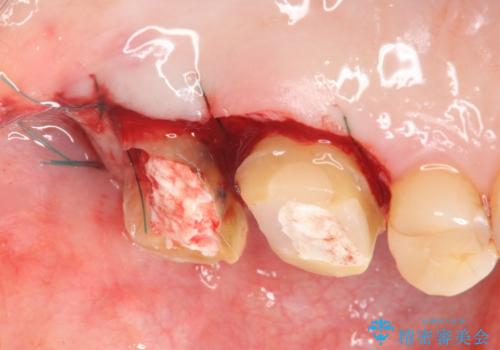

・深い虫歯 →歯周外科を行うことで歯ぐきの腫れを改善

・根尖性歯周炎 →精密根管治療

・咬合機能の回復 →セラミッククラウンの製作

と問題点を一つづつ丁寧に解決し、長期的に虫歯が再発せず安定を見込める治療を行っていきます。